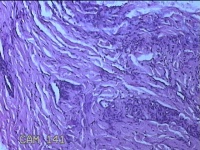

左侧中指皮下结节

性别

女

年龄

32岁

临床诊断

皮下结节

一般病史

发现左侧中指皮下结节1年余。

标本名称

大体所见

灰白暗红色肿物0.5x0.3x0.2cm两个,表面糜烂。